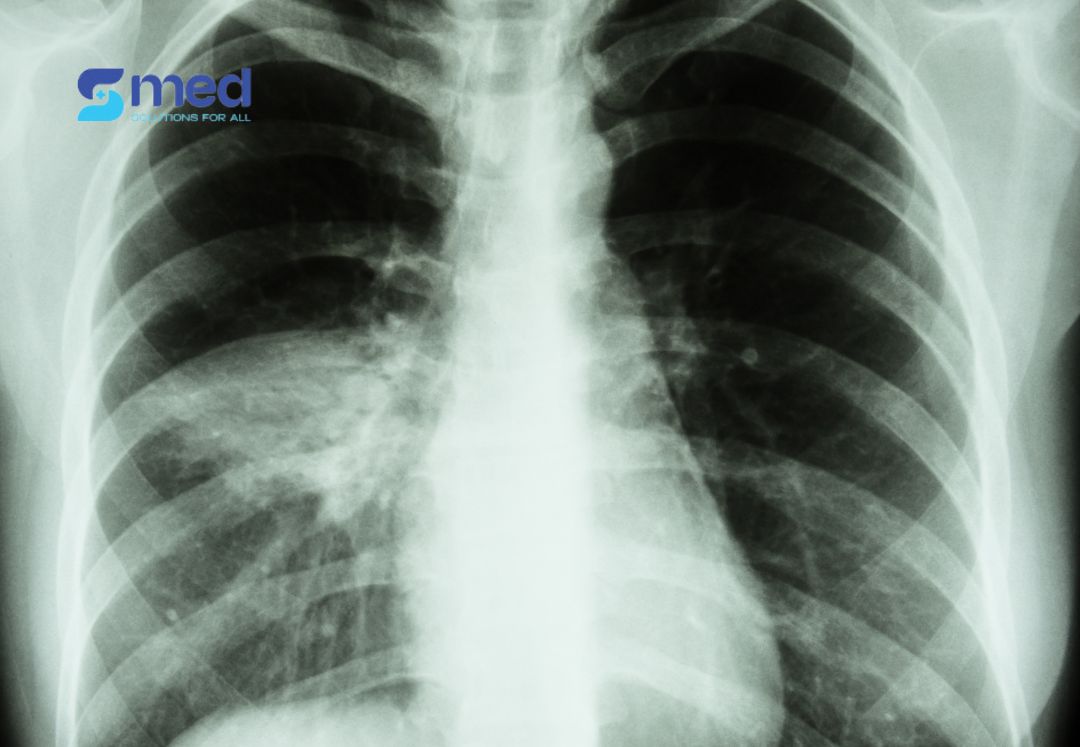

Thâm nhiễm đáy phổi là tình trạng mô phổi vùng đáy (thấp nhất của phổi) xuất hiện những chất bất thường như dịch, tế bào viêm, mủ hoặc tế bào ung thư. Trên phim X-quang hoặc CT ngực, vùng này hiện lên như các mảng trắng đục, là dấu hiệu cho thấy phổi đang bị tổn thương hoặc viêm nhiễm nghiêm trọng.

Vì vậy, việc phát hiện sớm qua hình ảnh học (X-quang, CT, siêu âm phổi), kết hợp theo dõi chức năng hô hấp là cực kỳ quan trọng. Thâm nhiễm đáy phổi không phải là một bệnh đơn lẻ, mà là dấu hiệu cảnh báo các vấn đề tiềm ẩn – đôi khi có thể phục hồi được nếu xử lý kịp thời, nhưng cũng có thể để lại hậu quả vĩnh viễn nếu chậm trễ.